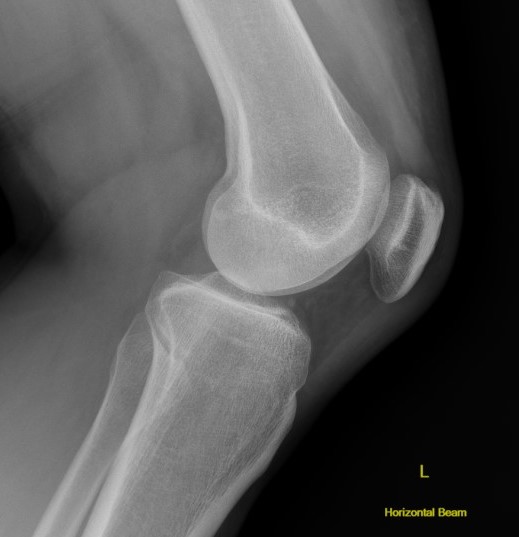

Bony Avulsion

Chronic bony avulsion PCL

Posterior subluxation of tibia